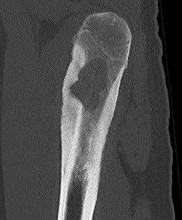

CT

Lucent lesion with nidus or calcification

Spinal lesion

- bone expansion

- intralesional stippled ossification